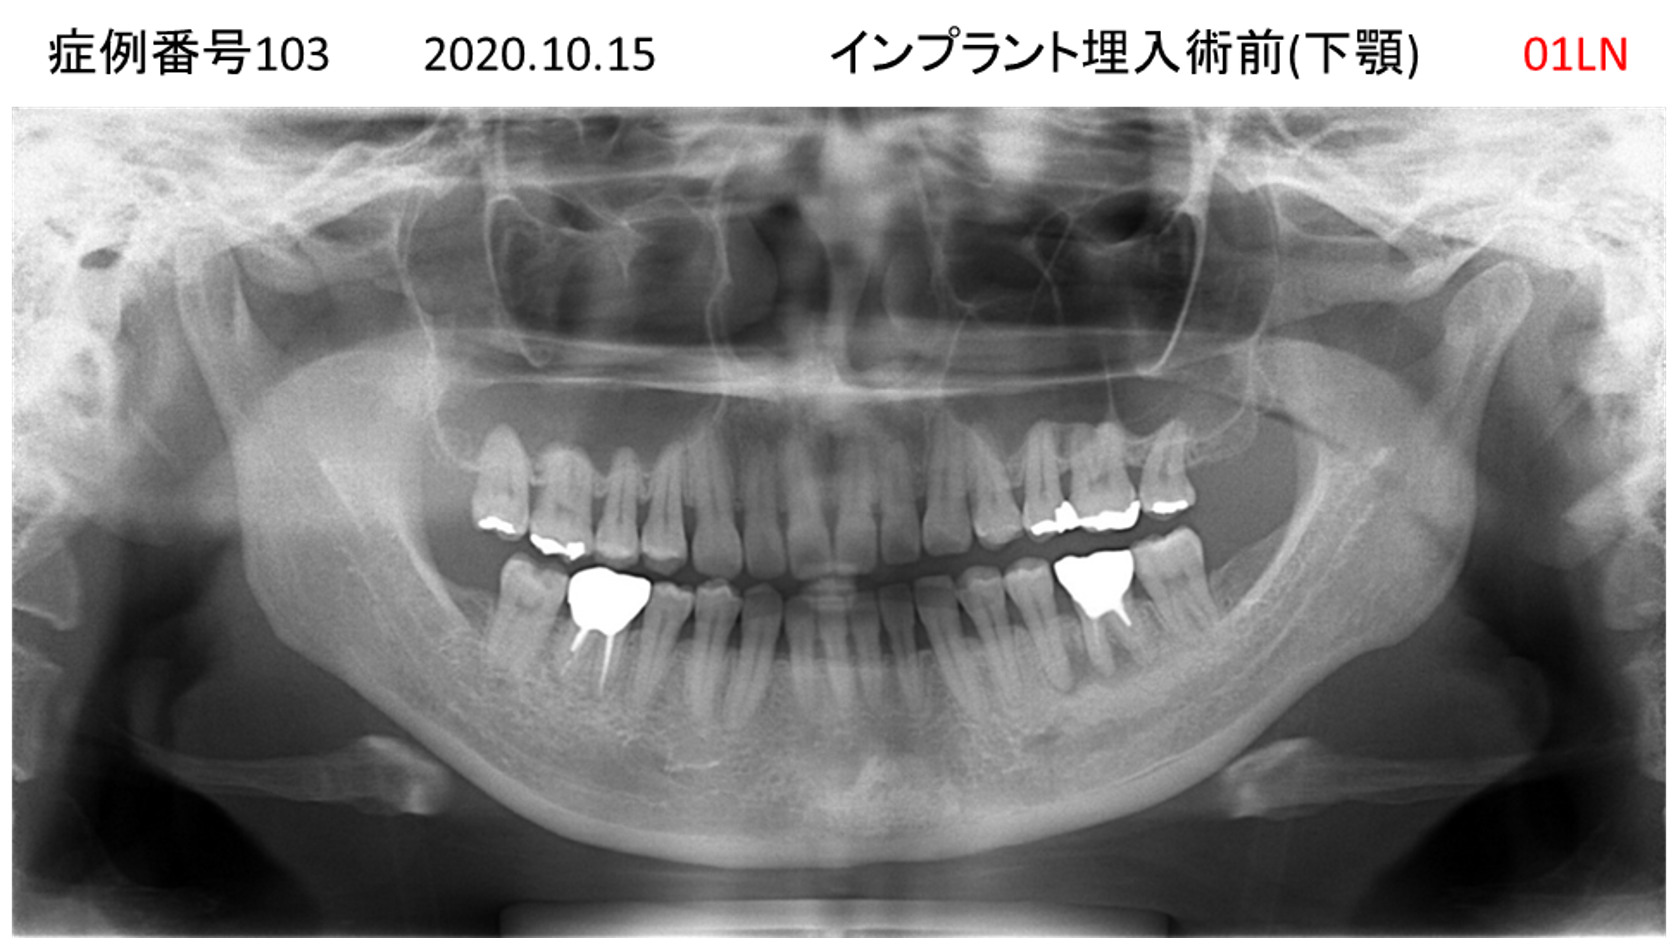

奥歯で噛めない患者様のインプラント症例

| 治療名称 |

インプラント |

| 治療費用 |

200万円+税 |

| 治療期間 |

4か月 |

| 患者さんの症状(主訴) |

奥歯で噛めない。 |

| 治療内容 |

| 治療結果 |

固いものもしっかり噛める。見た目がとても良くなった。 |

| 治療の注意点(リスク/副作用) |

インプラントが壊れたら再治療が必要 |